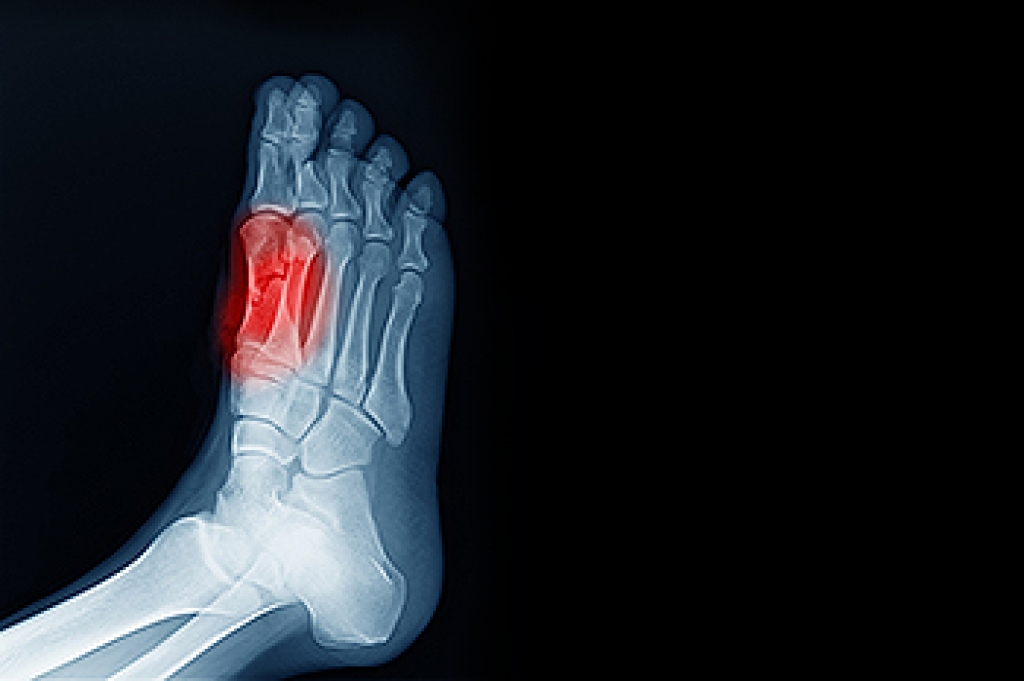

A broken pinky toe is a fracture of the smallest toe, often caused by stubbing it against furniture, dropping a heavy object, or sports injuries. Symptoms can include sharp pain, swelling, bruising, and difficulty walking or wearing shoes. Even though the pinky toe is small, a fracture can affect balance and gait, leading to additional foot strain. A podiatrist can confirm the diagnosis with an examination and imaging, provide proper immobilization, recommend supportive footwear, and guide recovery to prevent complications. They may also address any misalignment to ensure proper healing. If you have broken your pinky toe, it is suggested that you promptly consult a podiatrist who can accurately diagnose and treat this type of toe fracture.

A broken toe occurs when one or more of the toe bones of the foot are broken after an injury. Injuries such as stubbing your toe or dropping a heavy object on it may cause a toe fracture.